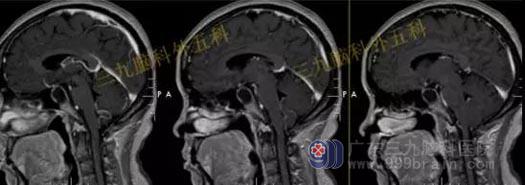

头部MR检查结果:鞍内及鞍上示一占位性病变,其内信号混杂,呈等或稍长T1稍长T2信号影,其内夹杂小片状短T1长T2信号影,增强后病灶呈明显不均匀强化;病灶范围约1.6cm×1.3cm×2.0cm;视交叉受压上抬,垂体柄受压右偏。

检查结果:鞍内及鞍上占位性病变,考虑为垂体大腺瘤合并卒中。

手术过程:患者今日在全麻下行内镜经鼻蝶鞍区垂体腺瘤切除术,术中肿瘤全切,垂体保护良好。

头部MR检查提示:鞍区病变已切除。

术前头部MR检查结果:鞍区示一团块状占位性病变,T1WI呈略低信号,T2WI呈稍高信号,增强后呈明显强化,病变界限清晰,边缘光整,范围约为3.1cm×2.7cm×2.0cm。病变示明显束腰征,垂体柄及视交叉受压显示不清,邻近颈内动脉受压移位,部分被包绕。

结果:鞍区垂体大腺瘤;病变部分包绕邻近颈内动脉。

手术过程:内镜下经鼻蝶鞍区垂体大腺瘤切除术,术中磨除鞍底,先行瘤内减压,双吸引器有序切除肿瘤,垂体及鞍隔保护良好,无脑脊液漏形成,肿瘤全切。

术后头部MR检查提示:肿瘤已全切。